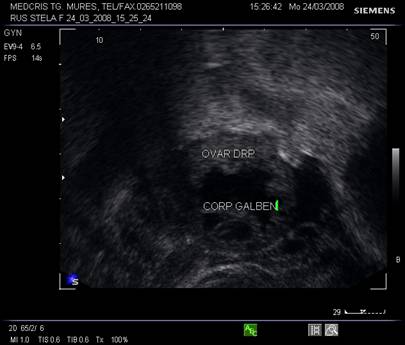

La pacientele care nu consuma contraceptive hormonale orale se pot identifica usor foliculii selectati preovulator sau corpul galben.

Semnele ecografice postovulatorii [2,6,9]

Ovarul

foliculul nu se mai observa in tensiune

foliculul colabat

aparitia corpului luteal

vascularizatie crescuta periferica la ecoDoppler

Fig. Nr.373. Corp galben recent, ziua a XV a de ciclu menstrual , prima zi postovulator. Se remarca aspectul ratatinat, anecogenitatea interna asociata cu fine puncte avand ecogenitate medie .( ecografie transvaginala )